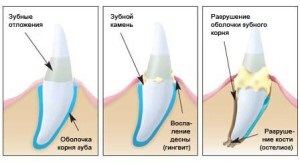

Az okok a fogínyvérzés

Ha vérezni kezdett, és fáj az íny - ez lehet a jele, fogágybetegség. A tényezők, amelyek provokál fejlődését periodontális betegség közé tartoznak bizonyos krónikus betegségek, örökletes vagy szerzett:

következő tünetek A periodontitisz szimptómái például: vérzés és duzzanat az íny, a mobilitás vagy lazítás és stripping a nyakára fogak, a interproximális redukció történik partíciókat. Íny sápadt, laza, könnyen megsérül.

Fogínyvérzés periodontitis közben történik a napi higiéniai, valamint a szilárd élelmiszer - chips, dió és alma.

periodontitis

Ha erősen vérző és ínygyulladás, - akkor beszélhetünk a fejlesztési periodontitis. a betegség tünetei közé tartozik még:

Okai fogágybetegség tartják a következő tényezők:

Ha az íny vörös, gyulladt és duzzadt - az oka az lehet jó néhány, ezek a következők:

- fogkő - traumatize szöveti történik vérzést okoz, és a fogíny duzzanata;

Az első tünetek a betegség

Ha a vérzés és duzzadt íny, azt tapasztalja, hogy a következő kapcsolódó tünetek: